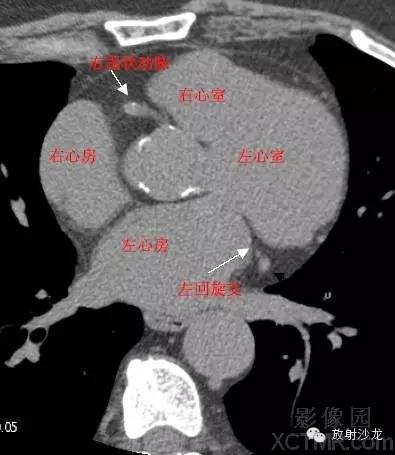

心脏冠状动脉CT解剖中文详细标注

LA -Left Atrium左心房

RA -Right Atrium右心房

LV -Left Ventricle左心室

RV -Right Ventricle右心室

LMA -Left Main Artery冠状动脉左主干

LCX -Left Circumflex Artery左回旋支